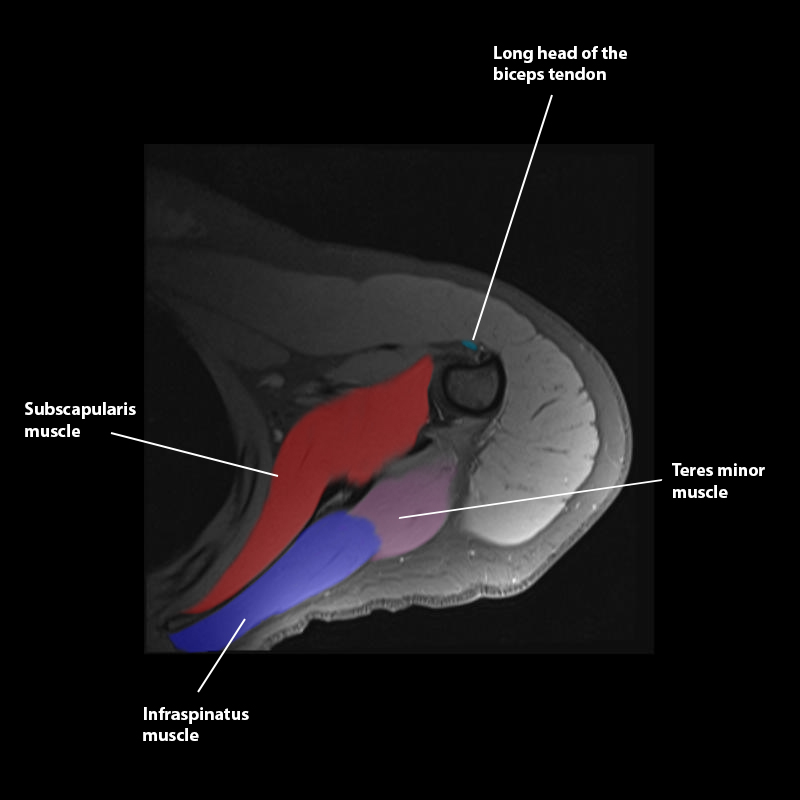

Shoulder MRI Anatomy